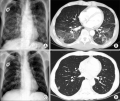

Pneumocystis carinii pneumonia in gastric cancer patients without acquired immune deficiency syndrome: 3 cases report and literature review. Yoon SY, Ki HK, Kim SY, Cho YH, Lee HG, Yoo MW - Journal of the Korean Surgical Society (2012)

| current | 17:36, 2 December 2021 | 512 × 433 (234 KB) | Rossdonaldson1 (talk | contribs) | Pneumocystis carinii pneumonia in gastric cancer patients without acquired immune deficiency syndrome: 3 cases report and literature review. Yoon SY, Ki HK, Kim SY, Cho YH, Lee HG, Yoo MW - Journal of the Korean Surgical Society (2012) |